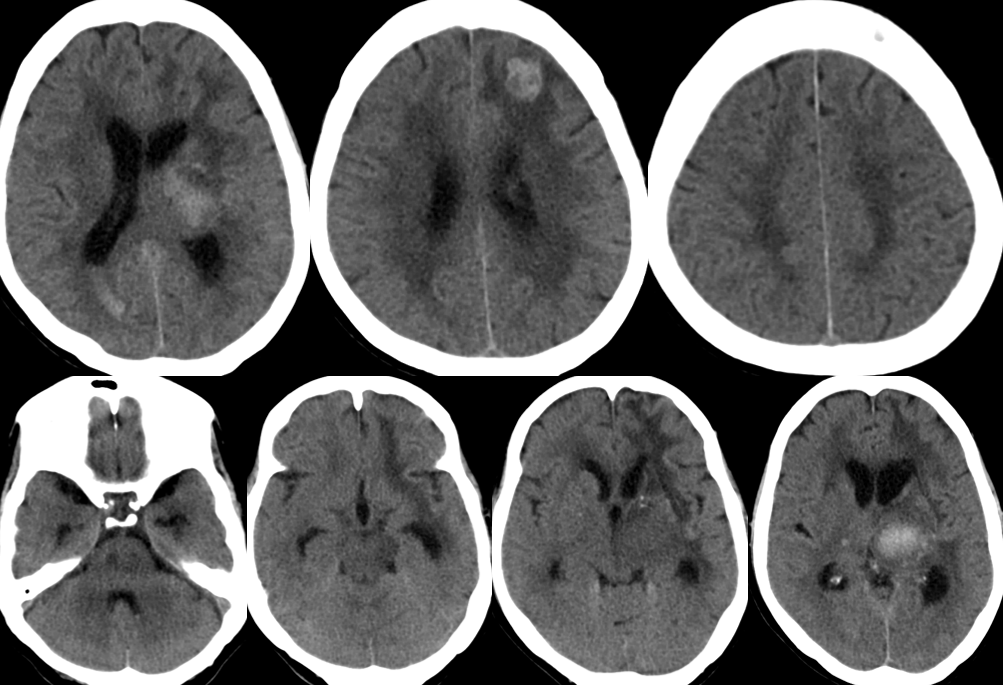

2014-12-2 CT

患者生命征平稳,精神可,一般情况好。

神经系统检查:神清清醒,有遵嘱动作,反应稍迟钝,左侧瞳孔2.5mm,右侧瞳孔3mmm,对光反射均稍迟钝,右上肢肌力粗测约2级,右下肢肌力粗测约3级,肌张力正常,左侧肢体肌力及肌张力粗测正常,右侧巴氏征阳性,余神经系统查体不能配合。

转院康复治疗。